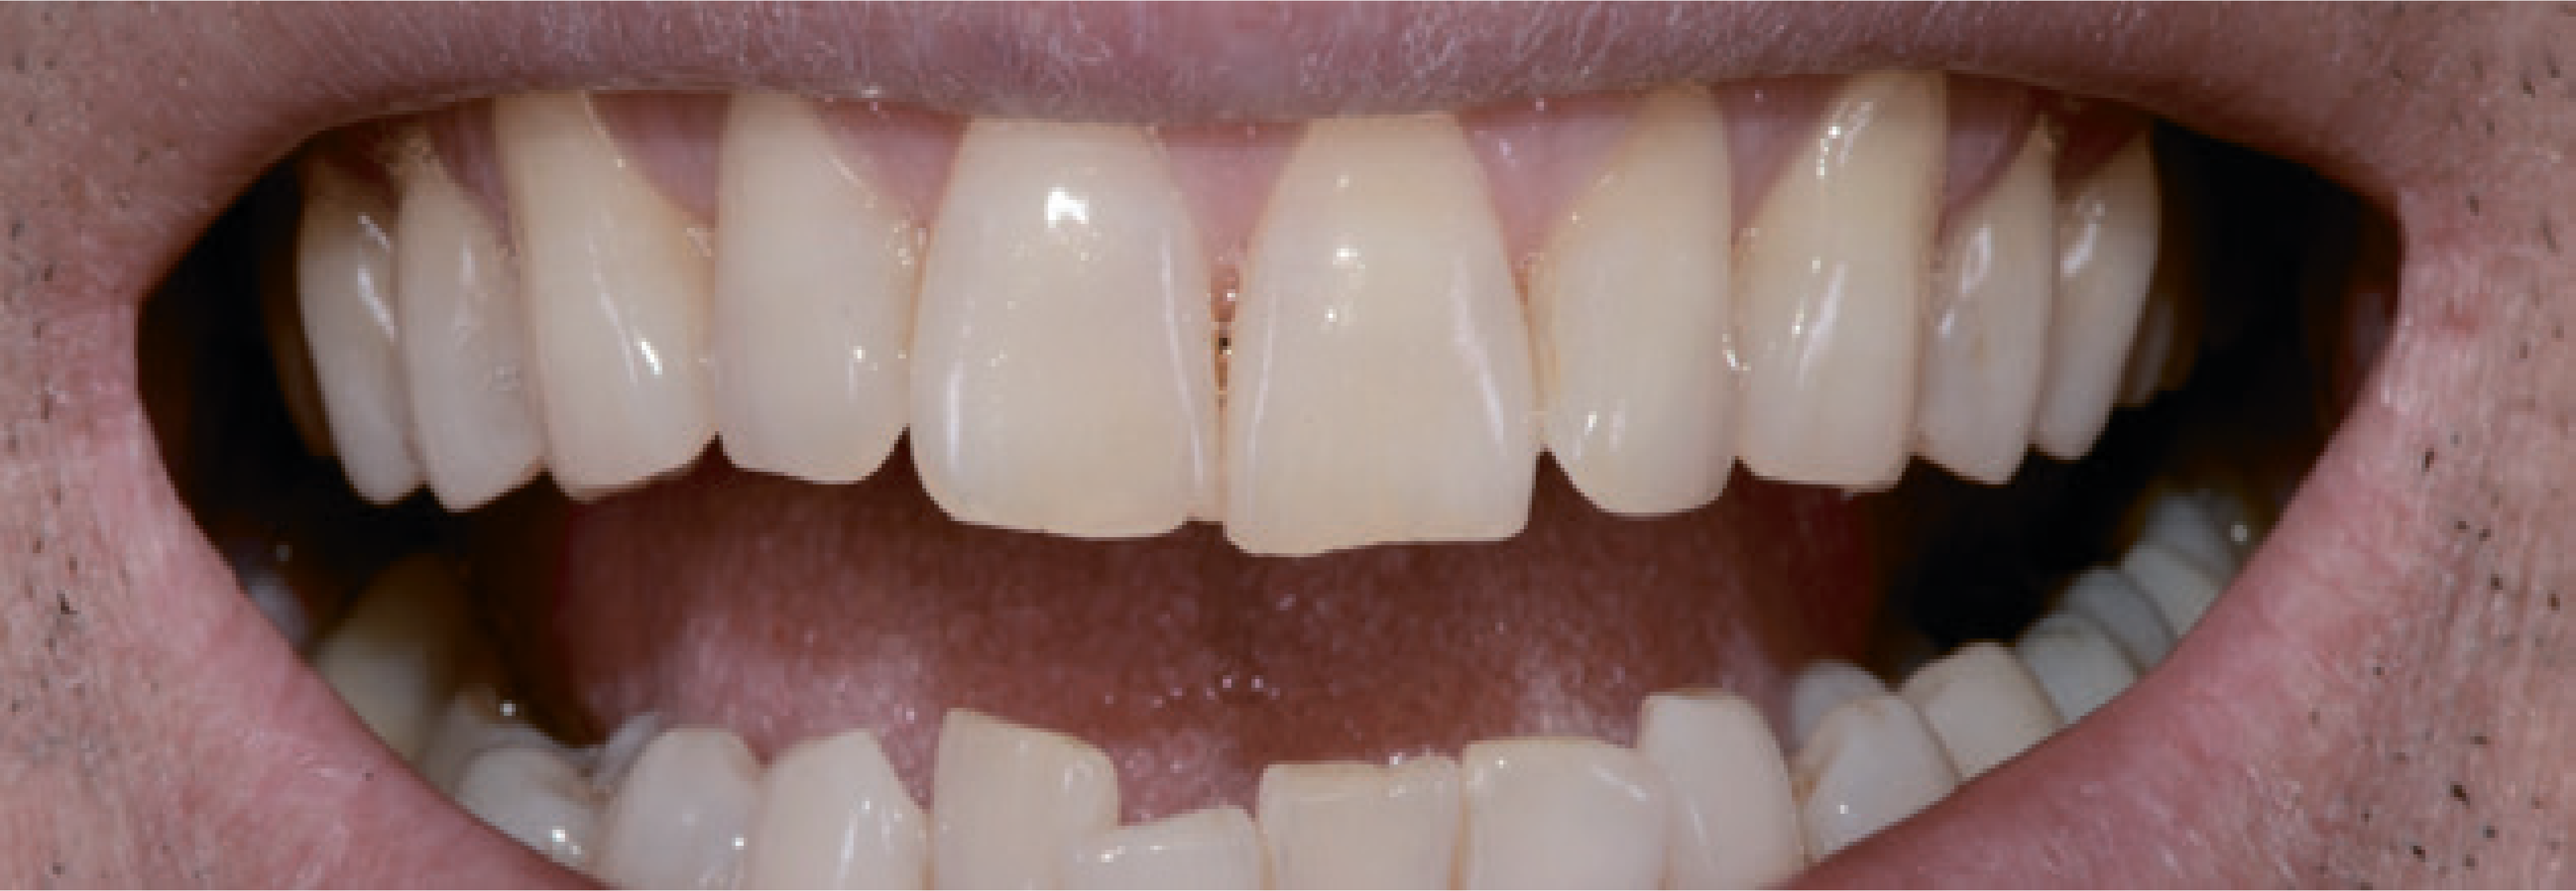

До стоматологічного кабінету звернувся 50-річний чоловік, незадоволений виглядом своїх зубів (мал. 1).

Загалом, він скаржився на жовтуватий колір і дистоповане положення зубів верхньої та нижньої щелеп. На перших фотографіях помітні певні естетичні дефекти. Різальні краї верхніх центральних різців були на різних рівнях (мал. 2).

Так, верхній лівий центральний різець був подовжений, і на ньому були явні ознаки стирання. Крім того, ікла були стерті, і це призвело до відсутності фізіологічних орієнтирів. Через положення верхньої губи під час посмішки було видно рівний ясенний край і правильну середню лінію на верхній щелепі, тимчасом як зуби нижньої щелепи були розташовані дуже близько один до одного (мал. 3).

Множинні гінгівальной рецесії були присутні переважно в естетичній зоні, за винятком лівих верхніх різців. Центральні різці, тобто 11, 21 і 22, були вивернуті із зубної дуги. В області різців нижньої щелепи була скупченість, і загалом вони занадто помітно виступали, були нахилені та зміщені. Проблем функціонального характеру пацієнт не відчував. Розбіжностей між центральним мищелковим положенням і стандартною інтеркуспідацією не було. Водночас безперечно було потрібно ортодонтичне лікування нижніх зубів. Стосовно функціонування, стерті ріжучі краї іклів потрібно було відновити, щоб відтворити природний осьовий напрямок ікла.